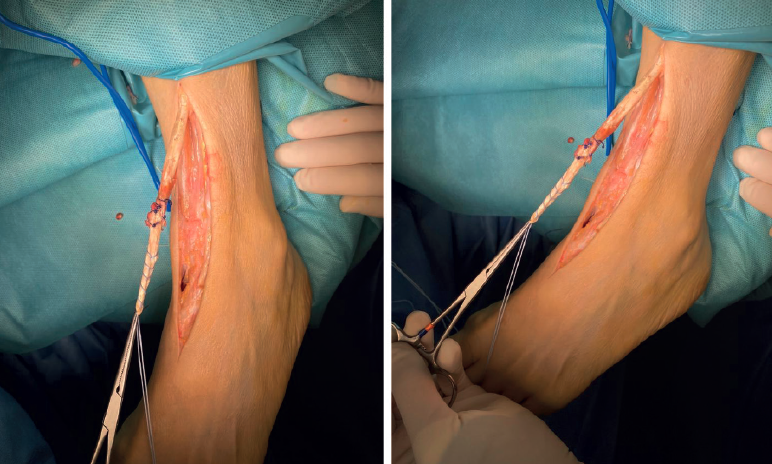

Se realizó una incisión anteromedial, en eje con el tendón TA, constatando que el cabo distal tendinoso se encontraba proximal al retináculo extensor dorsal inferior. Se procedió entonces a la apertura de este y a la posterior resección del cabo distal degenerado. Al finalizar la exposición quirúrgica, el acortamiento tendinoso era de 9 cm, con pobre traslación a la tracción (Figura 2). Se decidió entonces realizar una técnica de turn down flap en el tercio medio del cabo tendinoso proximal (Figura 3), desdoblando así el tendón y obteniendo un aumento considerable de su longitud (Figura 4). Ante la imposibilidad de reanclar el tendón a la cuña medial, se realizó una fijación en el escafoides tarsiano con un tornillo de biotenodesis, que cedió a la tensión y sufrió un arrancamiento. Finalmente, se obtuvo el anclaje definitivo en el cuello del astrágalo con un tornillo de biotenodesis (Figura 5). Por último, se realizó un cierre por planos con especial atención en la reparación del retináculo extensor.